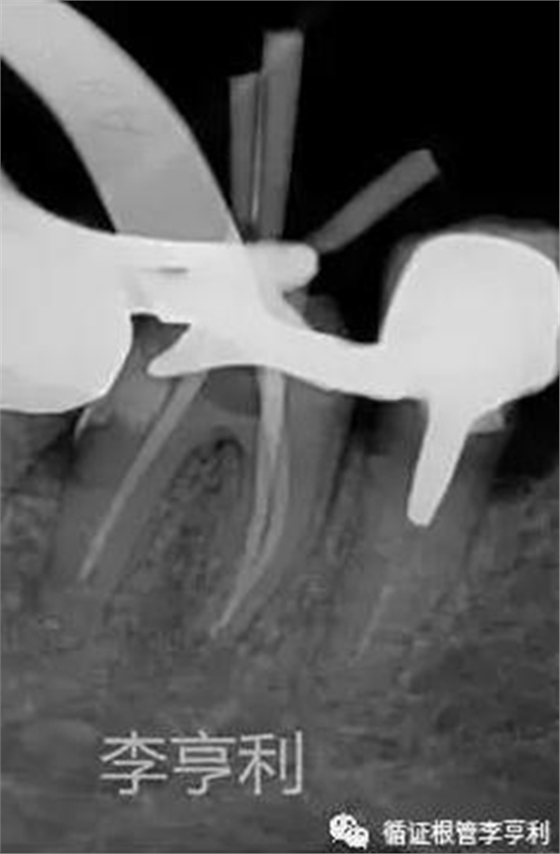

暴露器械斷端 (2017-06-26)

器械被超聲震出 (2017-06-26)

分離器械約為4mm長(zhǎng) (2017-06-26)

治療過(guò)程:由于患者根管系統(tǒng)較細(xì)窄,無(wú)法建立旁路疏通MB根,因此決定取出分離的器械。首先在顯微鏡下暴露器械斷端,然后使用超聲工作尖震動(dòng)斷針,30分鐘內(nèi)斷針被順利震出,然后疏通MB到根尖。之后就常規(guī)完成剩余根管治療步驟,轉(zhuǎn)回進(jìn)行后續(xù)冠修復(fù)。